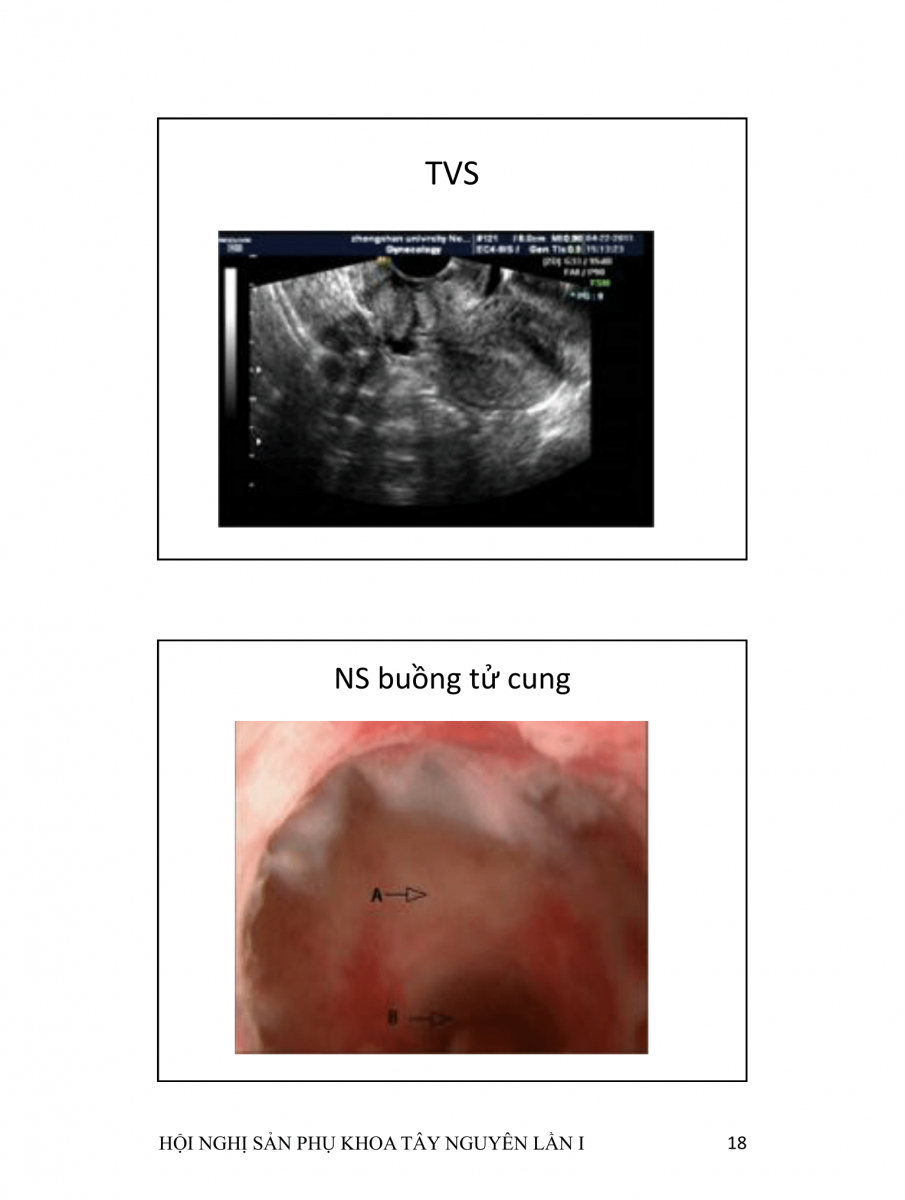

Hở khuyết sẹo mổ lấy thai  (CESAREAN SCAR DEFECTS)